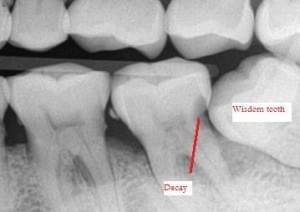

- Impacted Wisdom Tooth - Impacted wisdom tooth can be a tricky dental problem since it doesn't always cause symptoms while doing severe damage to other teeth. The problem usually happens between the ages of 17 and 25. - Common symptoms of impacted wisdom tooth: - Swollen gums at the back

- Problems you may get from an impacted wisdom tooth: - Damage to other teeth e.g. root resorption

- Tooth decay

- Gum diseases and bone loss

- Cyst/tumour (mostly benign)

- Crowding of other teeth

- How do I prevent impaction of wisdom tooth? - Unfortunately, it is not possible to control the position/angulation of how a wisdom tooth grows. Therefore, removal of wisdom teeth may be inevitable. One of the purposes of having regular dental visits and x-rays is to monitor the growth and emergence of wisdom teeth, evaluate the risk and detect problems earlier. - Golden rule: cost to repair damages caused with wisdom tooth impaction is higher than cost to remove impacted wisdom tooth